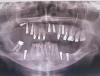

Tatijna Опубликовано 18 октября, 2013 Поделиться Опубликовано 18 октября, 2013 В феврале 2013г. поставили импалнты и сделали синус лифтинг на верхнюю десну справа.К лету получила гайморит,один имплант свалился в пазуху.В октябре 2013-операция радикальная гайморотомия ,свищ,повторная операция,опять свищ.Сказали,что ткани очень рыхлые,поэтому швы не держатся.Посоветовали отдых на 10 дней,потом делать третью аналогичную операцию.На данный момент после второй операции швы не сняты,свищ на месте шва,зато сняты все временные коронки.Мучениям нет конца.В добавок несколько имплантов торчат в гайморову пазуху.Мой стоматолог не видит в этом ничего страшного,уверяет,что на них можно ставить коронки,надо только залечить свищ.А врач ЧЛХ,которая дважды оперировала меня,сказала,что удалять эти импланты возможно только во время третьей операции.Но как они ни штопают,они не могут зашить потом удачно мои рыхлые ткани.Так что оперироваться в своем городе не буду.Пока ищу по инернету специалиста в Москве или в Питере,хотелось бы получить ответ,неужели однозначно надо убирать эти импланты,которые смотрят в гайморову пазуху?Ведь мой стоматолог считает наоборот,а он лучший в нашем городе.И неужели,чтобы их удалить,необходимо опять вскрывать гайморову пазуху(третий раз за месяц!!!)как это считает моя ЧЛХ???Вот это снимок до операции,сейчас упавший имплант достали.Но на снимке хорошо видны верхние импланты справа,которые торчат в гайморову пазуху. Ссылка на комментарий

Tatijna Опубликовано 24 октября, 2013 Автор Поделиться Опубликовано 24 октября, 2013 Побывала у своего стоматолога в нашем городе.Он не видит проблемы в том,что два импланта торчат в пазуху..Считает,что гайморит и свищ случились только от того одного крайнего импланта,который упал в пазуху.А так как его достали во время операции гайморотомия,то проблема решена.Больше мне это не грозит.Осталось только залечить свищ и можно ставить коронки на эти импланты.Категорически не советовал их выкручивать.Попробовал их отверткой и сказал,что они стоят очень хорошо.Но теперь он заявил,что подсадка костной ткани мне и не нужна в этом месте.Вполне можно поставить на эти два импланта коронки и ещё навесной зуб.Зрительно будет всё ОК,не будет видно,что дальше у меня нет зубов.И не надо мучиться с подсадками(два синус лифтинга,которые он мне сделал,не прижились).Нормально!Но я ведь затеяла эту эпопею с подсадкой,чтобы не только избавиться от съемных бюгельных протезов,но и для того,чтобы выровнять челюсти.Левая верхняя челюсть опущена ниже правой,так как там есть свои зубы,жевала на них,вот и результат.Теперь,если воплотить в жизнь этот план моего стоматолога,и дальше придётся жевать на левой опущенной стороне.Такой вариант меня не устраивает.Собираюсь искать имплантолога в Питере,чтобы ещё раз сделать подсадку кости.У меня несколько вопросов к специалистам.Нет ли таких технологий,чтобы выполнить очередную подсадку,не выкручивая эти импланты?Я то думаю,что вынимать их придется,но вдруг прогресс уже так продвинулся вперед.На этих имплантах у меня стоят вкладки.Сложно ли будет их удалить?Охота знать к чему готовиться морально. Ссылка на комментарий

SergeyAL Опубликовано 25 октября, 2013 Поделиться Опубликовано 25 октября, 2013 имплантаты, которые "торчат" в пазуху не более, чем на 5 мм действительно не проблема - это мнение лор врачей. Но в Вашем случае, если был острый гайморит, то поверхность имплантатов, " торчащих" в пазуху могла инфицироваться и в таком случае, это уже проблема. То, что они интегрированы в данный момент времени не означает, что через 6 мес интеграция сохранится, и так же неэффективность санации пазух, говорит за то, что там находится инфекция (скорее всего на поверхности "торчащих" имплантатов). В данной ситуации рекомендую прислушаться к мнению челюстно-лицевого хирурга. Ссылка на комментарий